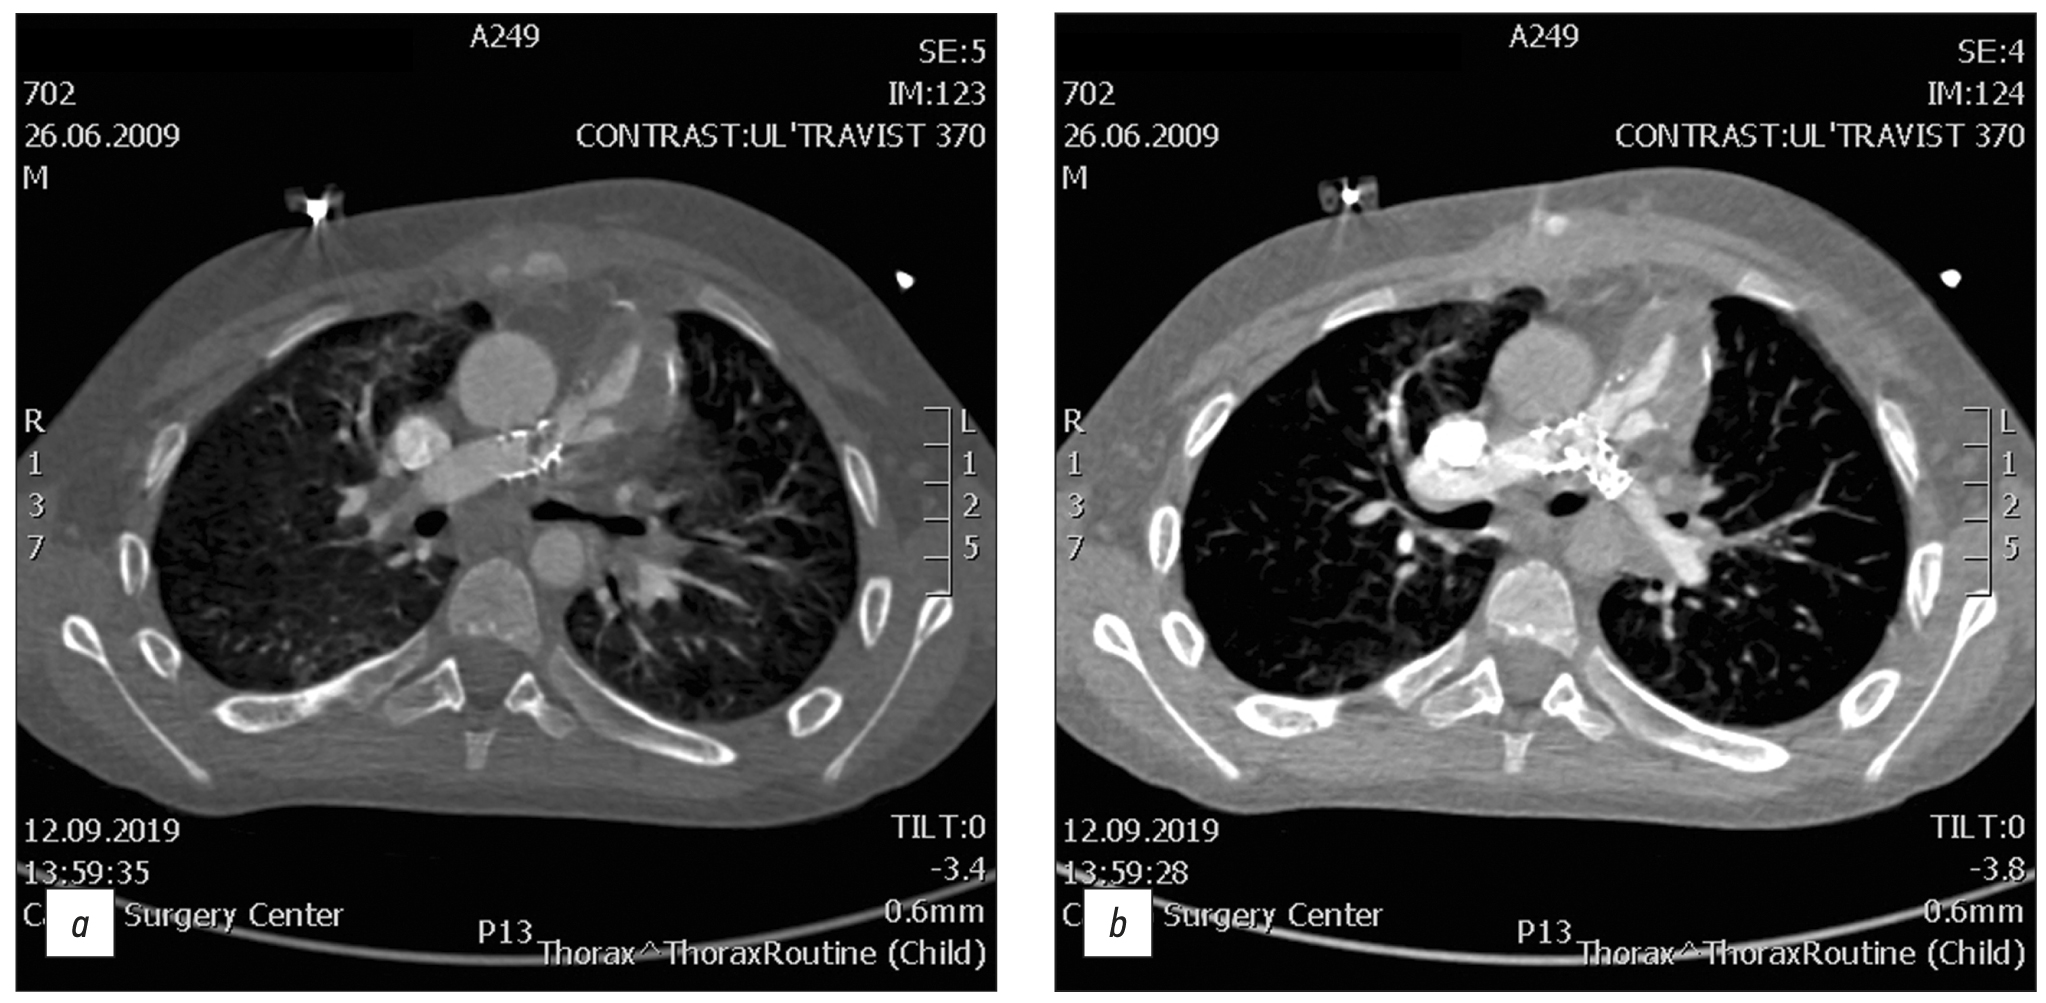

Fig. 1. CT of valve-containing conduit Contegra No. 16 and bilateral stents Palmaz Genesis XD 19-10.

A 12-year-old male with repaired tetralogy of Fallot, after implantation of valve-containing conduit Contegra No. 16 and bilateral stents Palmaz Genesis XD 19-10. Cardiac CT image clearly demonstrates thrombosis conduit. All the complications detected by CT were validated with angiography and were operated on.